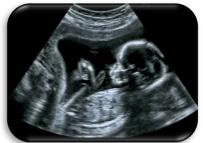

(ii) The diagram shows a foetus in the uterus (womb). Label the diagram, using the words provided in the table.

(iii) Read the paragraph below and answer the questions that follow:

Throughout pregnancy the mother may avail of prenatal and postnatal care.

Prenatal visits to a healthcare provider usually include a physical exam and a urine sample test. Depending on the stage of pregnancy, healthcare providers also do blood tests and imaging tests such as ultrasound exams.

Adapted from hse.ie

State a reason why any one of the following are carried out at prenatal visits to a healthcare provider.

Put a tick () in one box below to clearly indicate which one you have chosen.

(v) The image shows a human sperm cell being inserted into a human egg cell which occurs in a type of IVF (in vitro fertilisation) treatment.